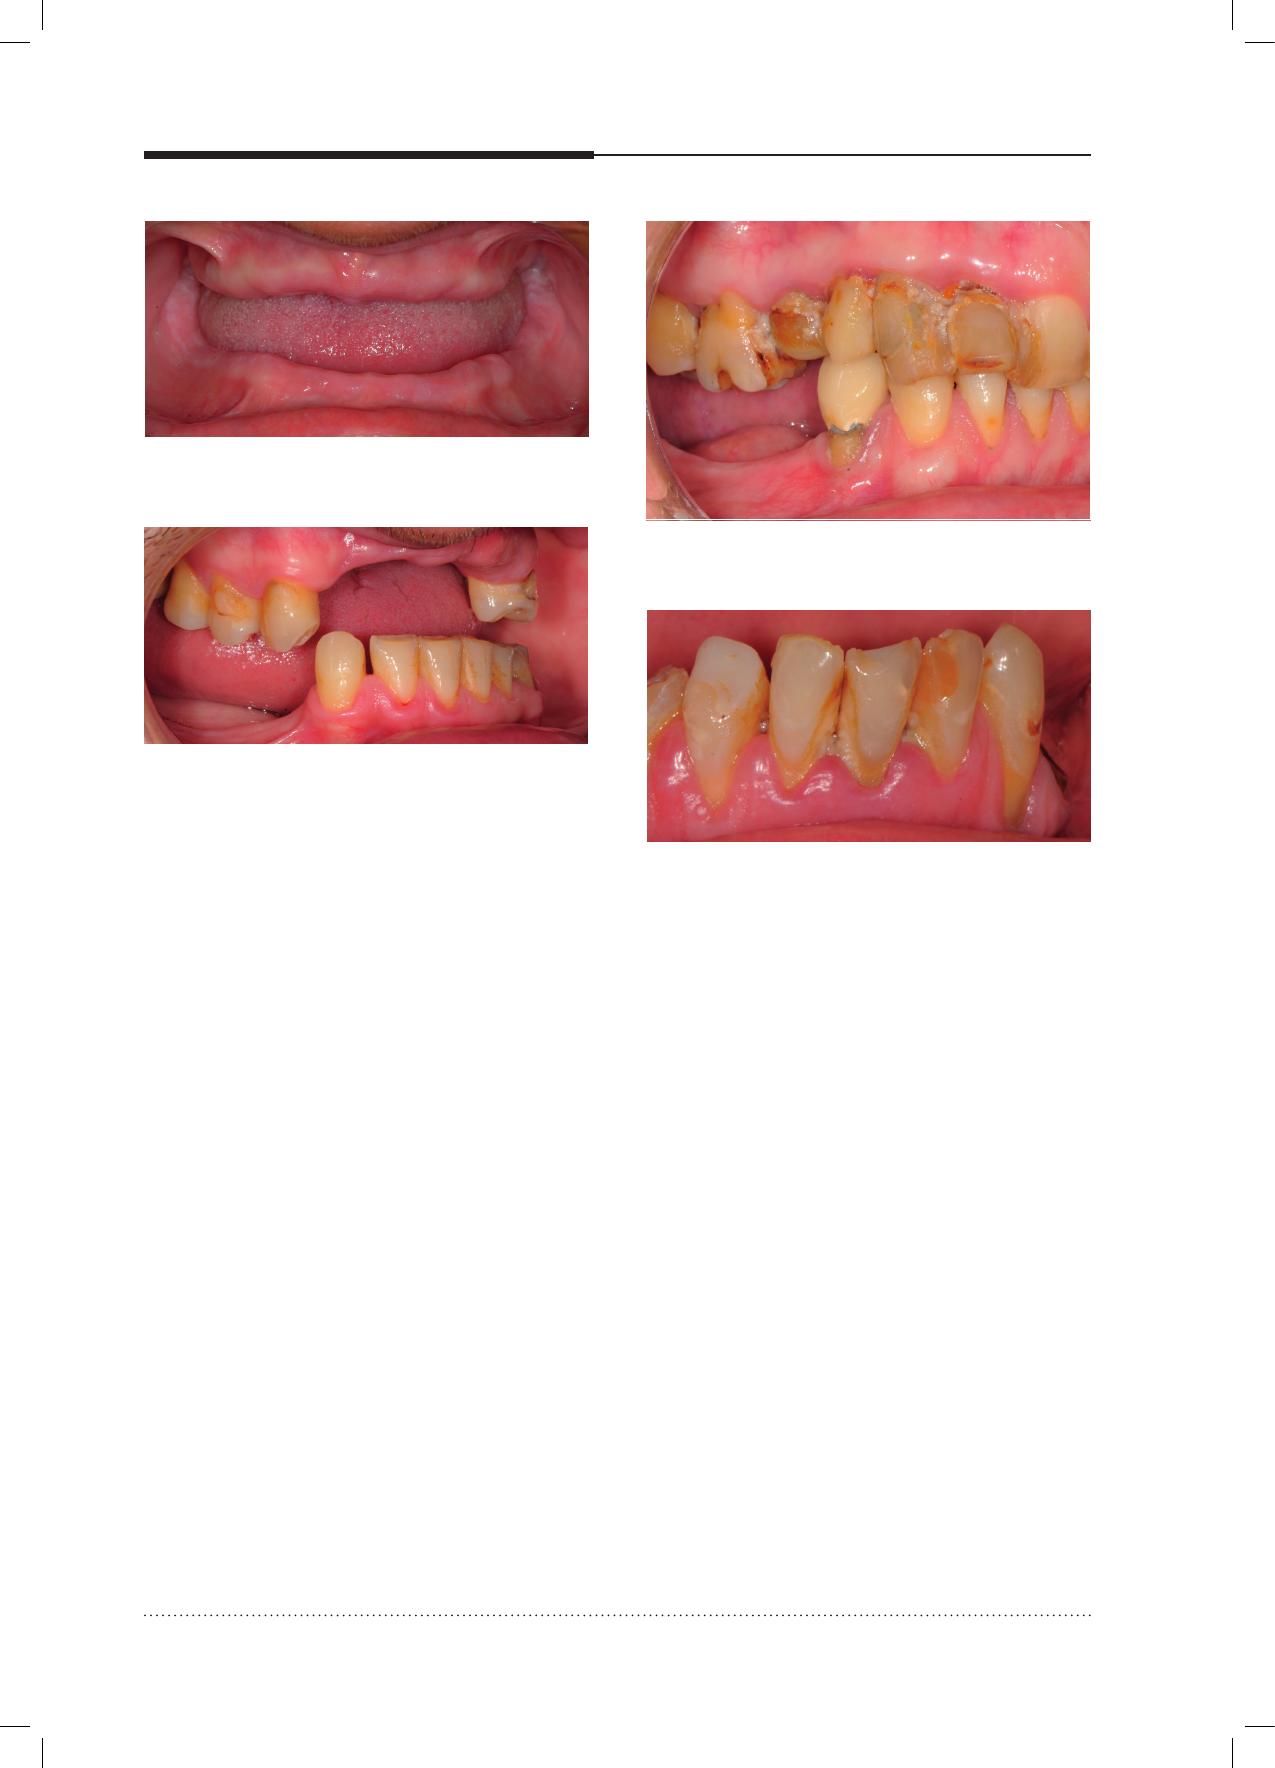

bucco-dentaires chez les sujets âgés est d’amé-

liorer leur hygiène dentaire et prothétique. Une

telle amélioration permettrait de prévenir les

caries et certaines pathologies muqueuses, mais

également les maladies parodontales. En insti-

tutions ou en milieu hospitalier, on constate, en

effet, que les soins d’hygiène dentaire et prothé-

tique sont peu ou pas réalisés par les personnes

âgées elles-mêmes et qu’ils ne sont que peu ou

pas du tout pris en charge par le personnel soi-

gnant. Ceci est, bien entendu, interpellant, car

lorsqu’un patient n’est pas en mesure d’assurer

son hygiène corporelle, logiquement celle-ci doit

être prise en charge par le personnel soignant.

Bizarrement, l’hygiène bucco-dentaire semble

«oubliée» dans ce cas.